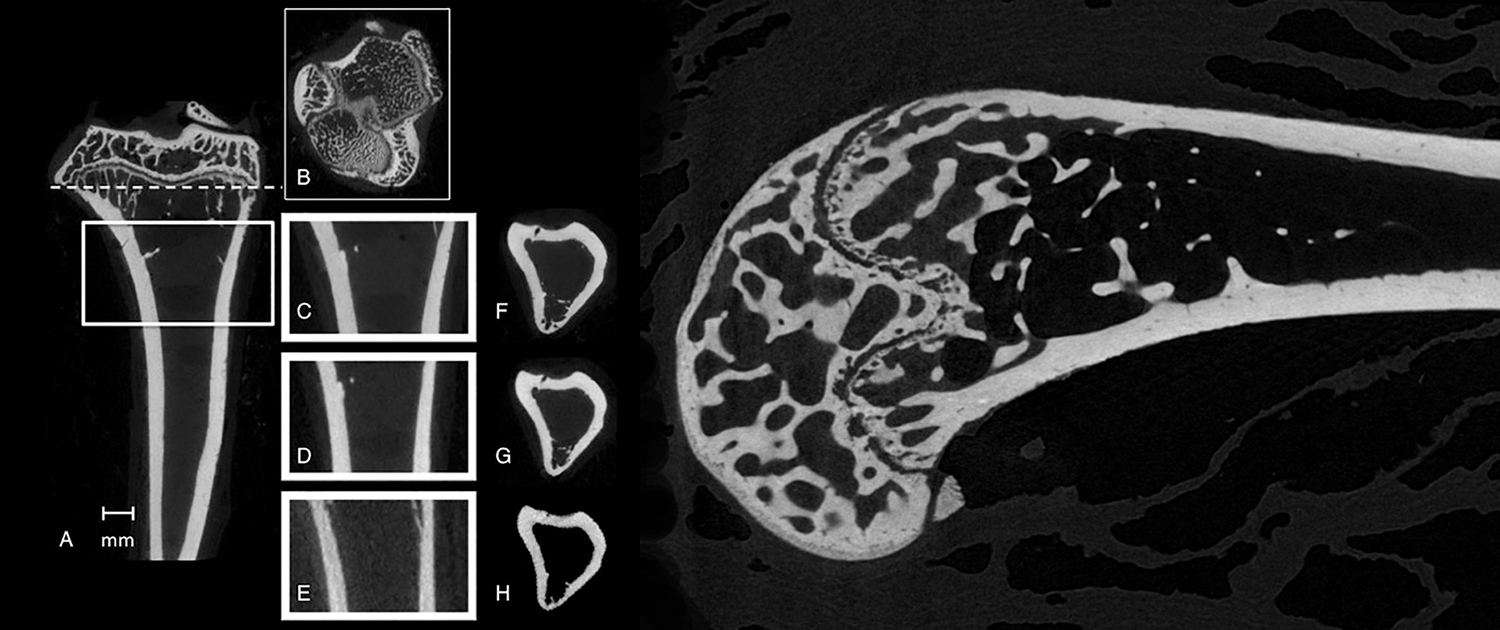

Micro-CT in Bone Studies

Bone Density Analysis

Micro CT can be used to assess bone density, which is a crucial parameter in evaluating bone strength and the risk of fractures. This application is important for the early diagnosis and treatment of osteoporosis and other bone disorders.

Bone Microarchitecture Assessment

Micro CT provides a detailed view of the bone’s internal structure, which allows researchers to evaluate the bone’s microarchitecture, such as trabecular thickness, spacing, and orientation. This information is essential for understanding the mechanical properties of bones and the effects of various treatments on bone health.

Internal Bone Structure Visualization

Micro CT provides detailed images of the internal structure of bones, which can be useful for investigating the anatomy and physiology of bones, as well as for studying the effects of various treatments on bone health.

Bone Disorder Investigation

Micro CT can be used to investigate the underlying causes of various bone disorders, such as osteoporosis, osteoarthritis, and other conditions. This information is important for developing new treatments for bone disorders and for improving the diagnosis and management of these conditions.

Micro-CT in Dental Research

Dental anatomy and morphology

Micro-CT is a powerful tool for studying the anatomy and morphology of the teeth and jaws. It can be used for the study of dental development and eruption, providing important information about the timing and sequence of tooth eruption, as well as the development of the dental arch. Additionally, micro-CT can be used for comparative dental anatomy, providing information about the evolution of teeth and the functional morphology of dental structures in different species.

- Tooth morphology analysis: Micro-CT can be used to analyze the internal and external morphology of teeth, including the roots and pulp cavities. This information is helpful in understanding tooth development and studying dental pathologies.

- Enamel analysis: Micro-CT can be used to analyze the thickness and mineral content of enamel, which is important for understanding the mechanical properties of teeth and for studying enamel-related diseases such as enamel hypoplasia.

- Dentin analysis: Micro-CT can also be used to analyze the structure and density of dentin, which is important for understanding the mechanical properties of teeth and for studying dentin-related diseases such as dentinogenesis imperfect.